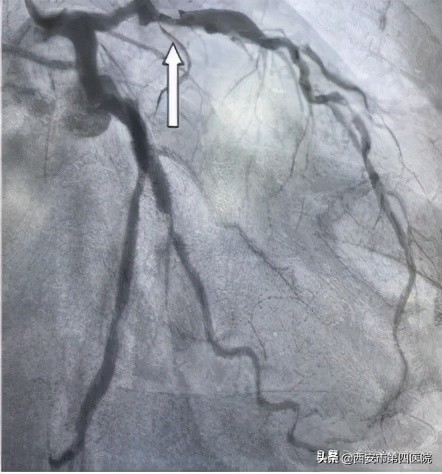

刘某术前-前降支重度狭窄

为了更精准了解管腔病变情况,经过由中国科学院科技服务网络计划重点项目自主研发的OCT检查后,发现刘某前降支中段狭窄处斑块负荷严重,斑块薄层纤维帽,存在脂质池,有随时发生破裂可能,管腔面积最小处仅为1.07mm2,提示血管严重狭窄。陈某右冠中段存在破裂斑块,与家属商议后,决定给予支架干预治疗。

刘某前降支术后